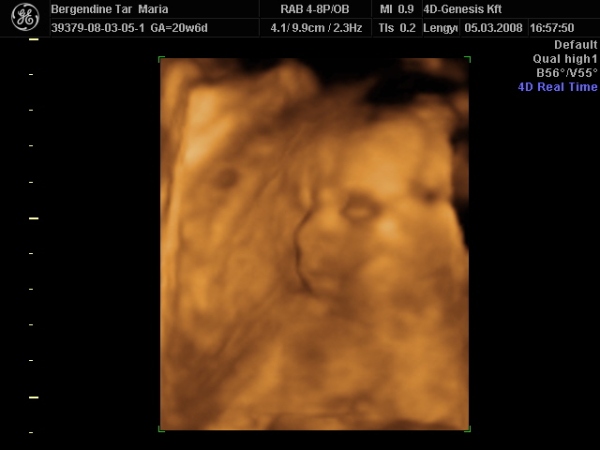

Hazaértem az ultrahangról, bemutatom nektek Zsófit:

Kép

édes a babád! Olyan mintha szopná az ujját, nem? :) A lányomnál már a 12 hetes ultrahangon úgy nézett ki, mintha szopná az ujját, aztán amikor megszületett, az első naptól kezdve szépen szabályosan szopta a hüvelykujját! Akkor lehet hogy mégis volt már gyakorlata benne???

Igen, a vizsgálat alatt csak néhány képen nem tömi az ujját a szájába. :lol:

végig ezzel volt elfoglalva. :lol: :lol: